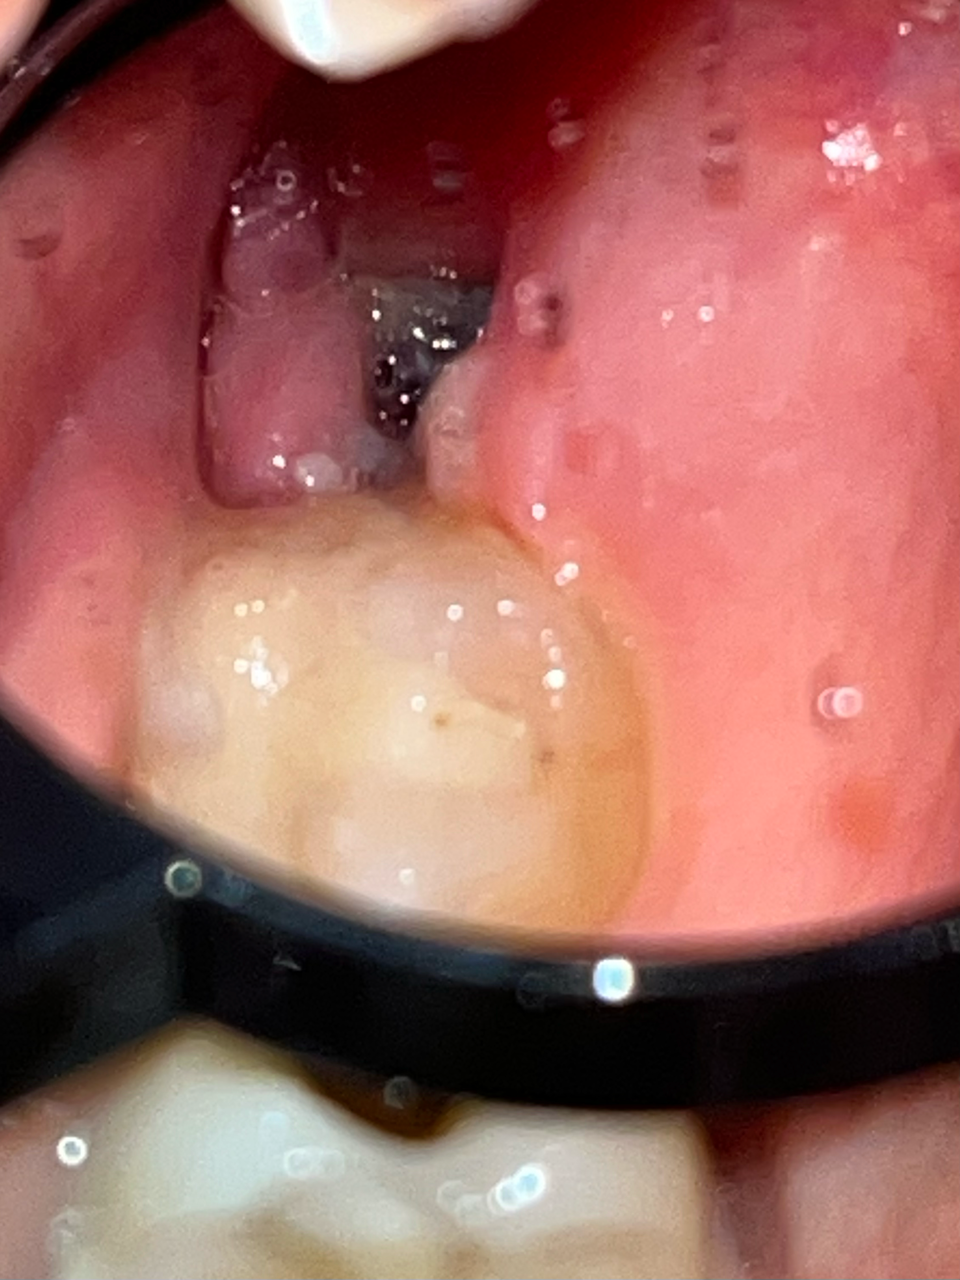

Хронические заболевания: не указаны

Здравствуйте, сегодня третий день после удаления верхнего зуба мудрости, удаление простое, без швов, зуб не ретинированный. Подскажите, пожалуйста, нормально ли проходит заживление и не похоже ли внешне на сухую лунку? К сожалению, лучших фото сделать не удалось. Вчера после чистки зубов было немного кровавой слизи после легкой ванночки хлоргексамедом. Боль слабая, при разговоре и жевании, купируется обезболивающим. Антибиотик не был прописан, контрольного обследования тоже не были назначено. Ем я мягкую пищу и рот не полоскала активно. Спасибо большое заранее за ответ и хорошего дня!

Добрый вечер.

На фото все нормально. Описание вашего состояние тоже соответствует норме. Если вы ожидаете развития альвеолита со стреляющими болям, то можно расслабится, т. к. на 4-ый день этого уже не произойдет.

"нормально ли проходит заживление" - Да, нормально.

"и не похоже ли внешне на сухую лунку? " - Нет, не похоже.